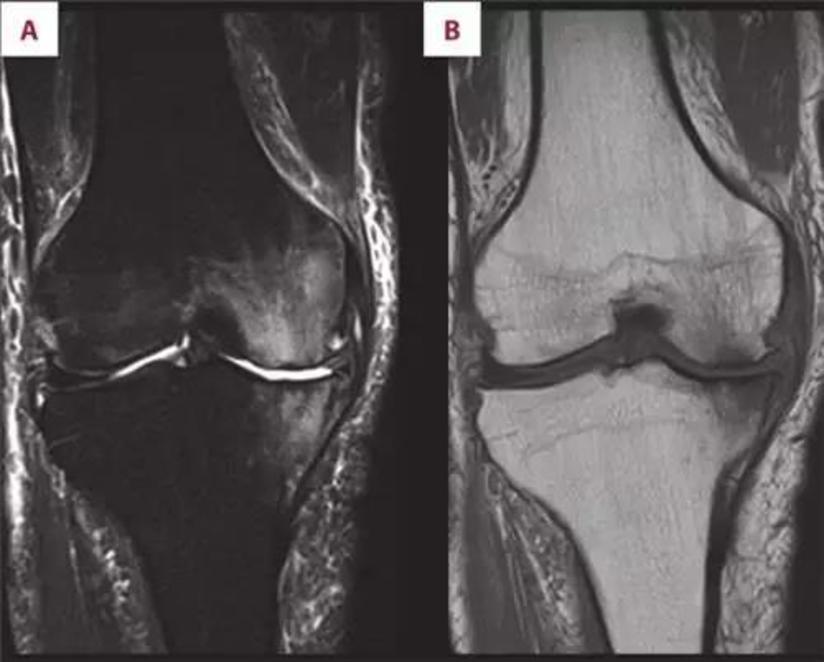

Ppt 骨关节病变mr 诊断powerpoint Presentation Free Download Id 4099169